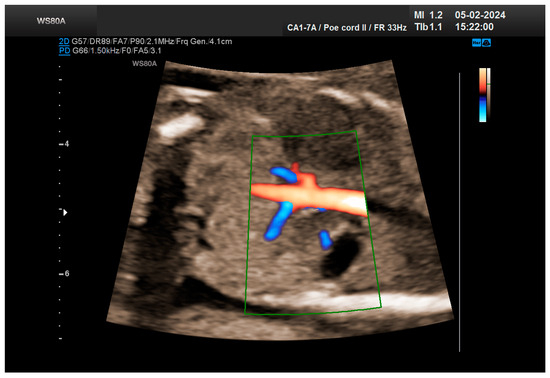

The patient returned at a gestational age of 22 weeks for a second-trimester ultrasound screening. During this examination, the suspicion of crossed fused renal ectopia was confirmed. Axial sections revealed a normal kidney image in the left lumbar fossa and another one, anterior to the spine, without reaching the right renal fossa, fused with the normal left kidney (Figure 5). Two sources of arterial vascularization could be identified, both of them with origins in aorta as follows: one correctly originating from the lumbar aorta, serving the normally positioned left kidney, and another appearing to originate on the anterior border of aorta, at the same level, supplying the ectopic right renal tissue mass (Figure 4 and Figure 6). The bladder was present, with normal appearance and volume. No left ureterohydronephrosis was detected. The presence and course of the right ureter could not be identified. The amniotic fluid volume was normal. No other severe or minor anomalies were observed.

Figure 4. The vascularization of the “renal mass” seems to originate in the aorta. Green box—color Doppler window.